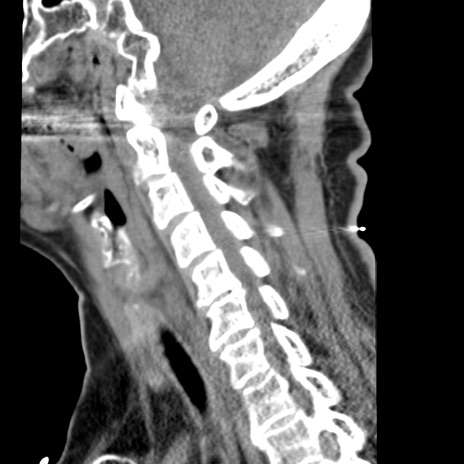

症例50 頚椎CT(矢状断像)

【症例】60歳代女性

【主訴】後頭部〜右後頸部にかけての痛み

【現病歴】本日飲食店でコーヒーを飲んでいたところ、突然後頭部〜右後頸部にかけて痛みが出現し、右上肢の感覚障害を伴ったため救急要請。

【身体所見】脳神経学的に明らかな異常所見を認めず。右上肢に軽度の感覚障害あり。

異常所見と診断は?

頚椎CT